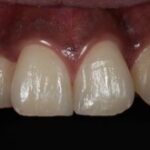

ダイレクトボンディングなどの

審美治療も高精度に対応